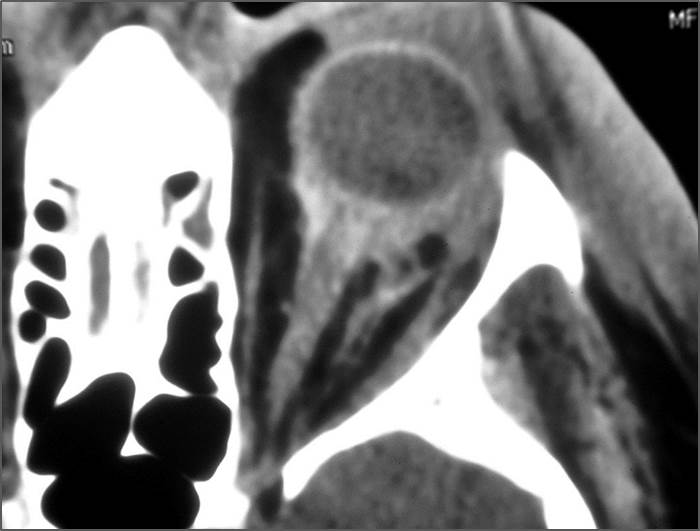

Eyes

Proptosis is present.

The optic nerve has a stretched appearance.

The posterior aspect of the globe is tented.

There are signs of a decompressed globe.

The lens is in abnormal position on either side.

There is evident general optic sheath swelling or swelling at the junction of the globe and sheath to suggest an optic sheath hematoma.